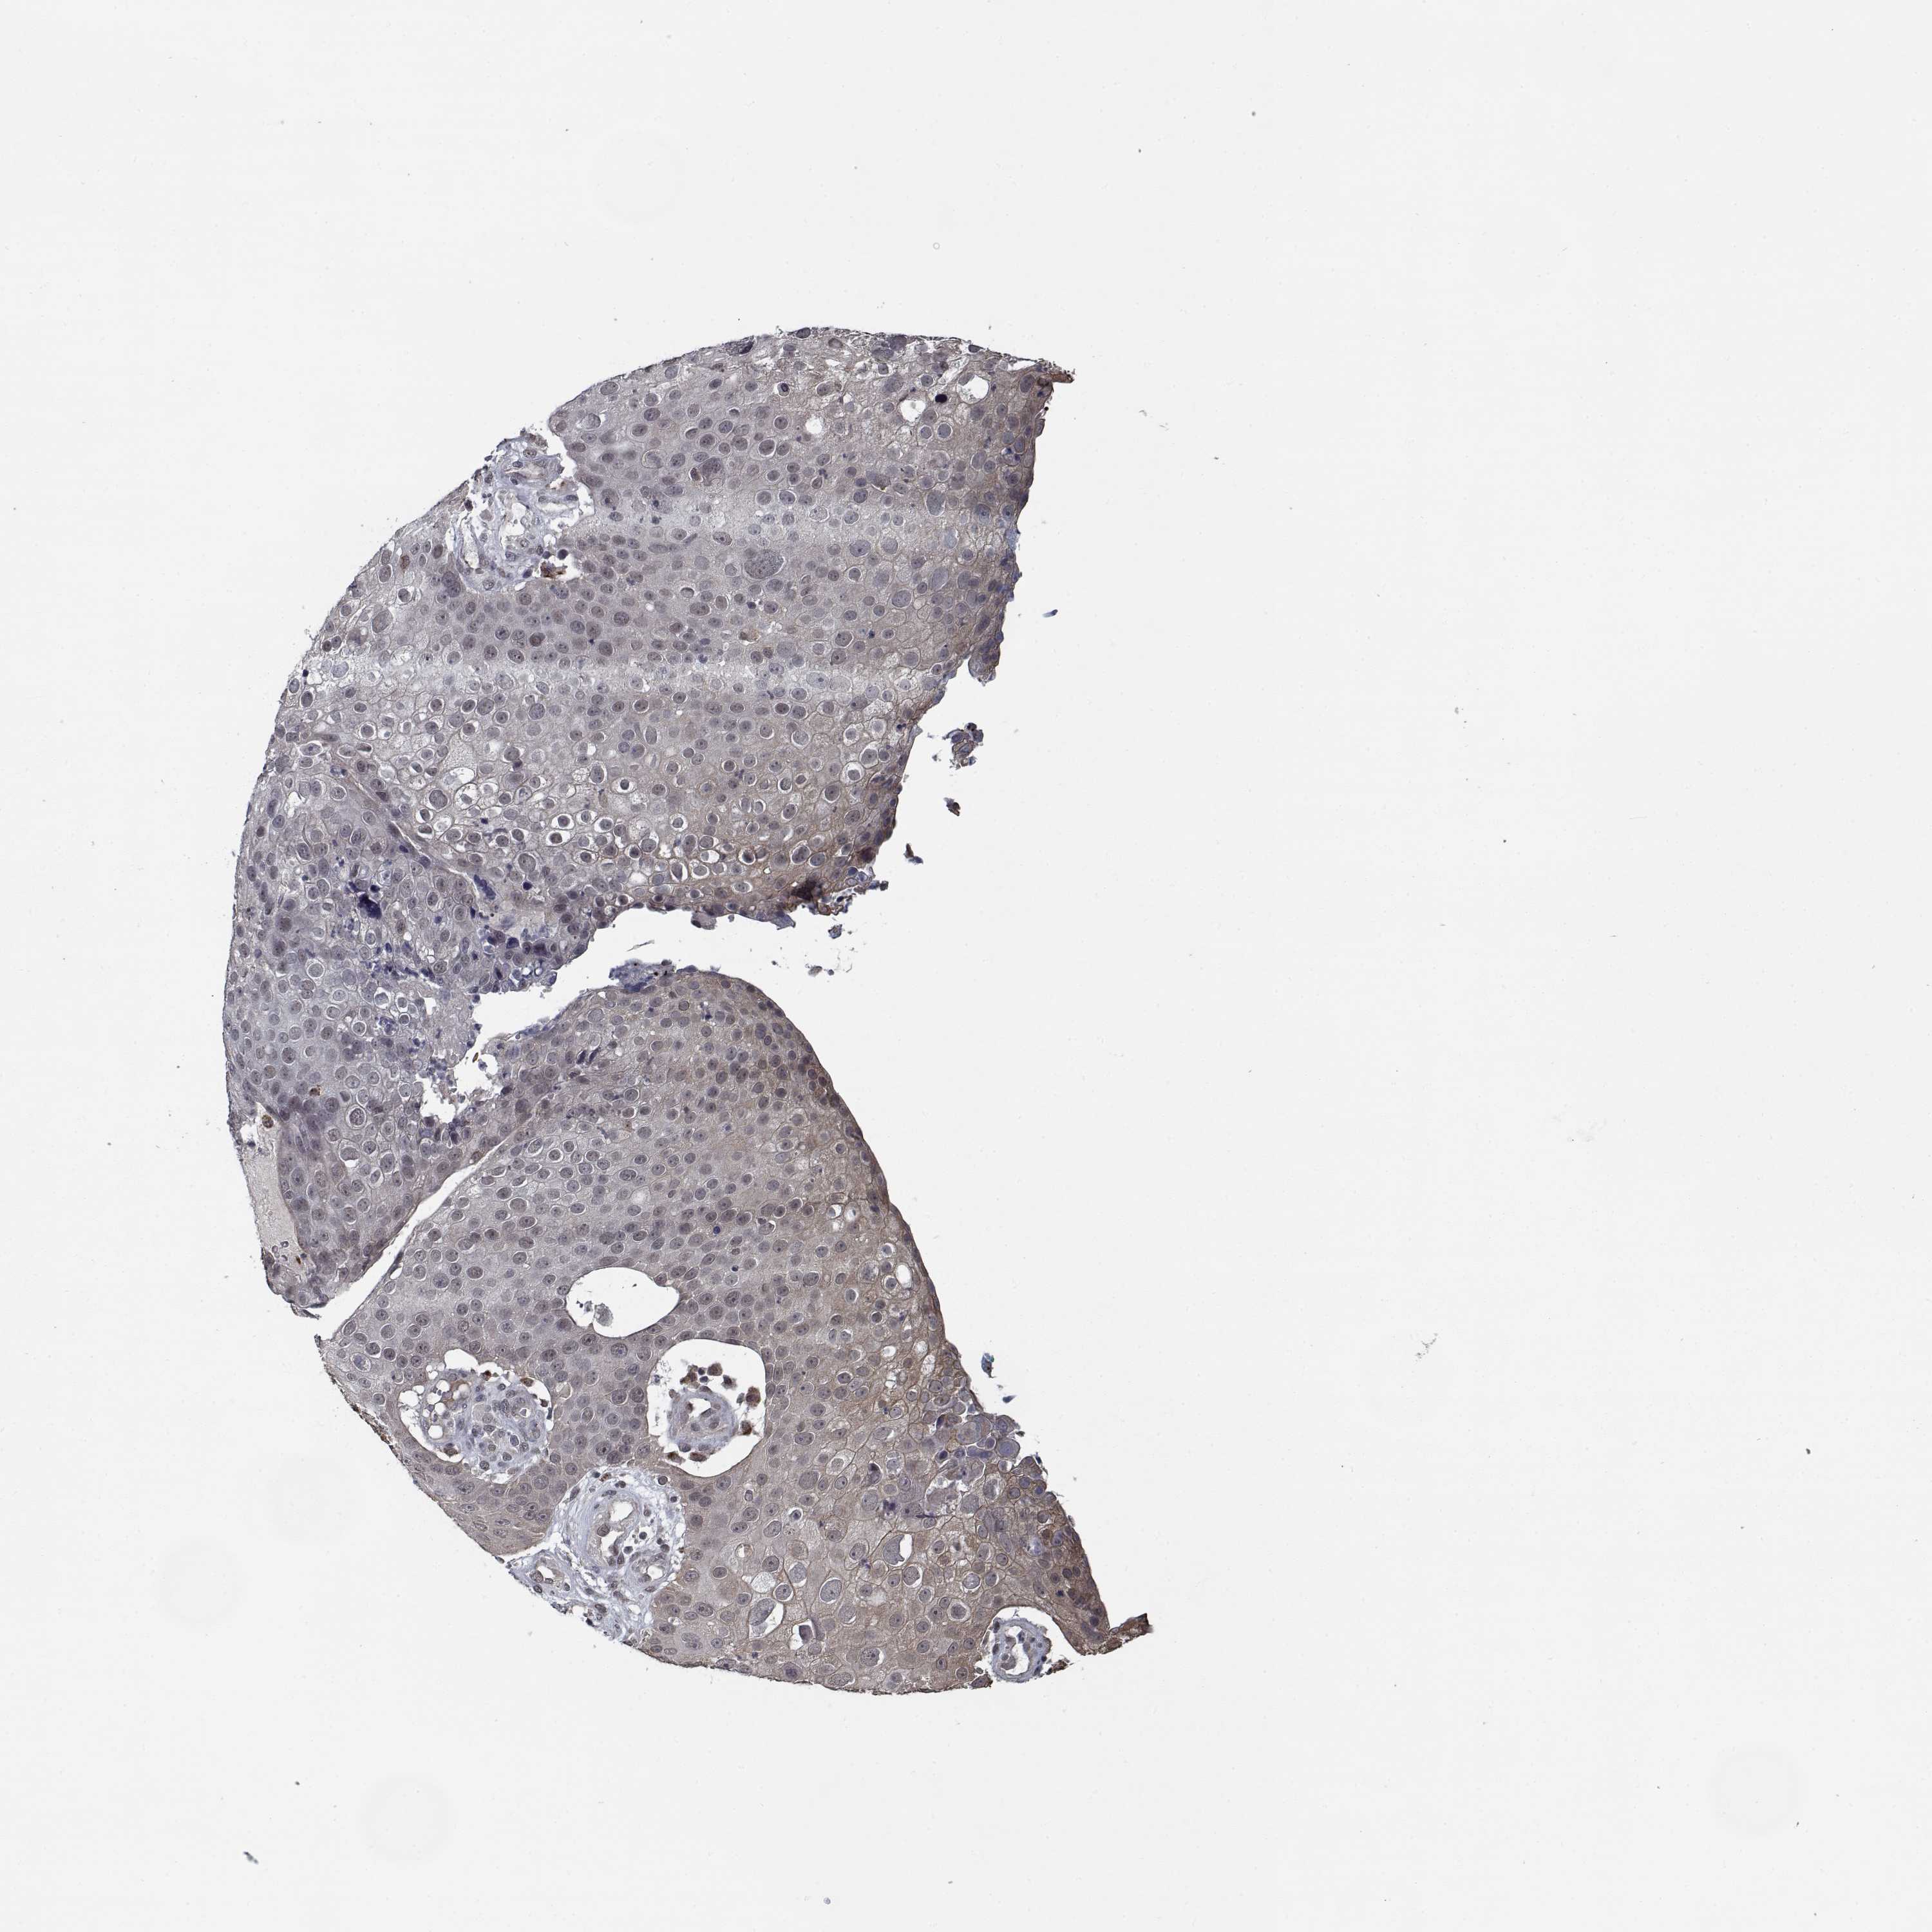

Basal cell and squamous cell cancer

SKIN CANCER - Protein expressioni

A mouse-over function shows sample information and annotation data. Click on an image to view it in a full screen mode. Samples can be filtered based on level of antibody staining by selecting one or several of the following categories: high, medium, low and not detected. The assay and annotation is described here.

Antibody stainingi

Antibody staining in the annotated cell types in the current human tissue is reported as not detected, low, medium, or high, based on conventional immunohistochemistry profiling in selected tissues. This score is based on the combination of the staining intensity and fraction of stained cells.

Each image is clickable and will lead to virtual microscopy that enables deeper exploration of all samples and also displays staining intensity scores, fraction scores and subcellular localization as well as patient and tissue information for each sample.

Antibody HPA056511

Staining

High

Medium

Low

Not detected

Intensity

Strong

Moderate

Weak

Negative

Quantity

>75%

75%-25%

<25%

None

Location

Nuclear

Cytoplasmic/membranous

Cytoplasmic/membranous,nuclear

Basal cell carcinoma